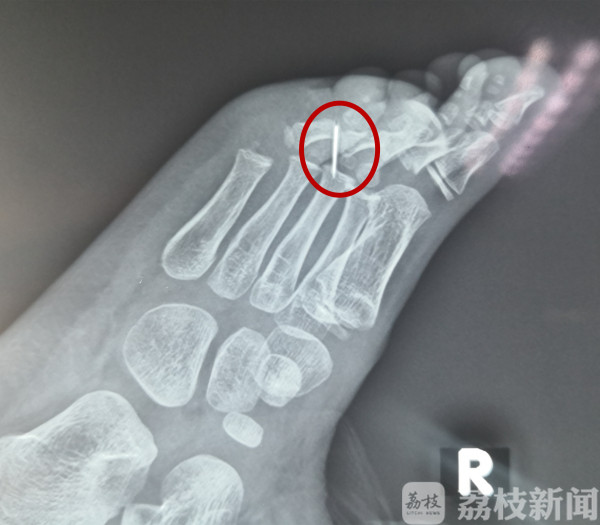

一截断裂的缝衣针,深深扎进了6岁男童昊昊(化名)的脚掌。在X光片上,断针清晰可见,但医生用了4个小时才将其取出,不是医术不高明,而是断针太“狡猾”,想尽办法给医生制造难题。

手术的每一步都是“如履薄冰”,医生们不断地对断针重新定位。“最终发现,断针在第二趾骨和第三趾骨的中间位置,扎的非常深,而且贴近骨膜了,确实不好找。”张友成说,最终历时4个小时才将断针取出。目前,昊昊恢复良好,很快就能出院了。